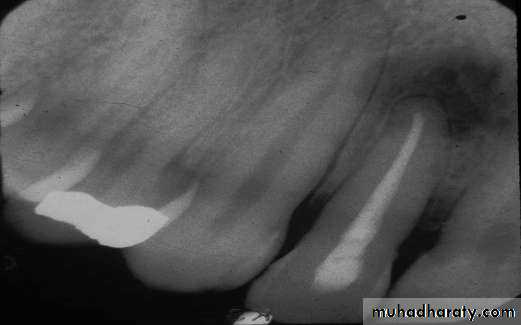

• Cementoblastoma

• Radiography:• Typically appears as radio opaque rounded mass with thin radiolucent margin.

• Attached to the root.

• Resorption of the related root is common.